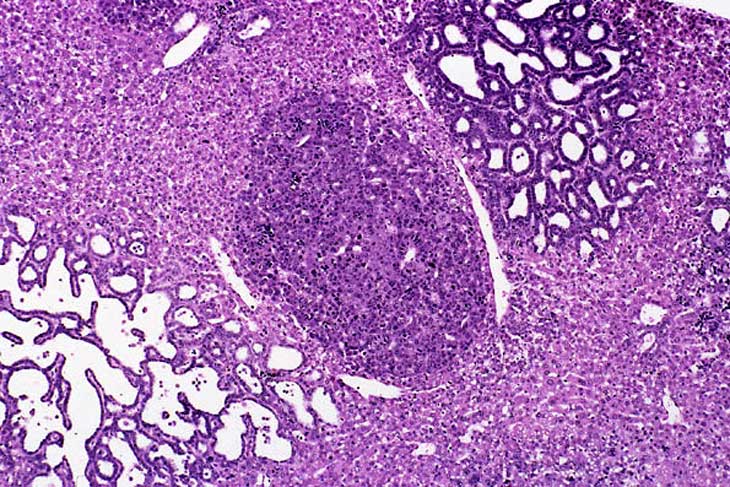

Hepatocellular adenoma and bile duct carcinoma in a 4-week-old transgenic mouse.

A proliferative cystic biliary lesion, a solid basophilic adenoma, and a bile duct adenoma in a 4-week-old transgenic mouse.